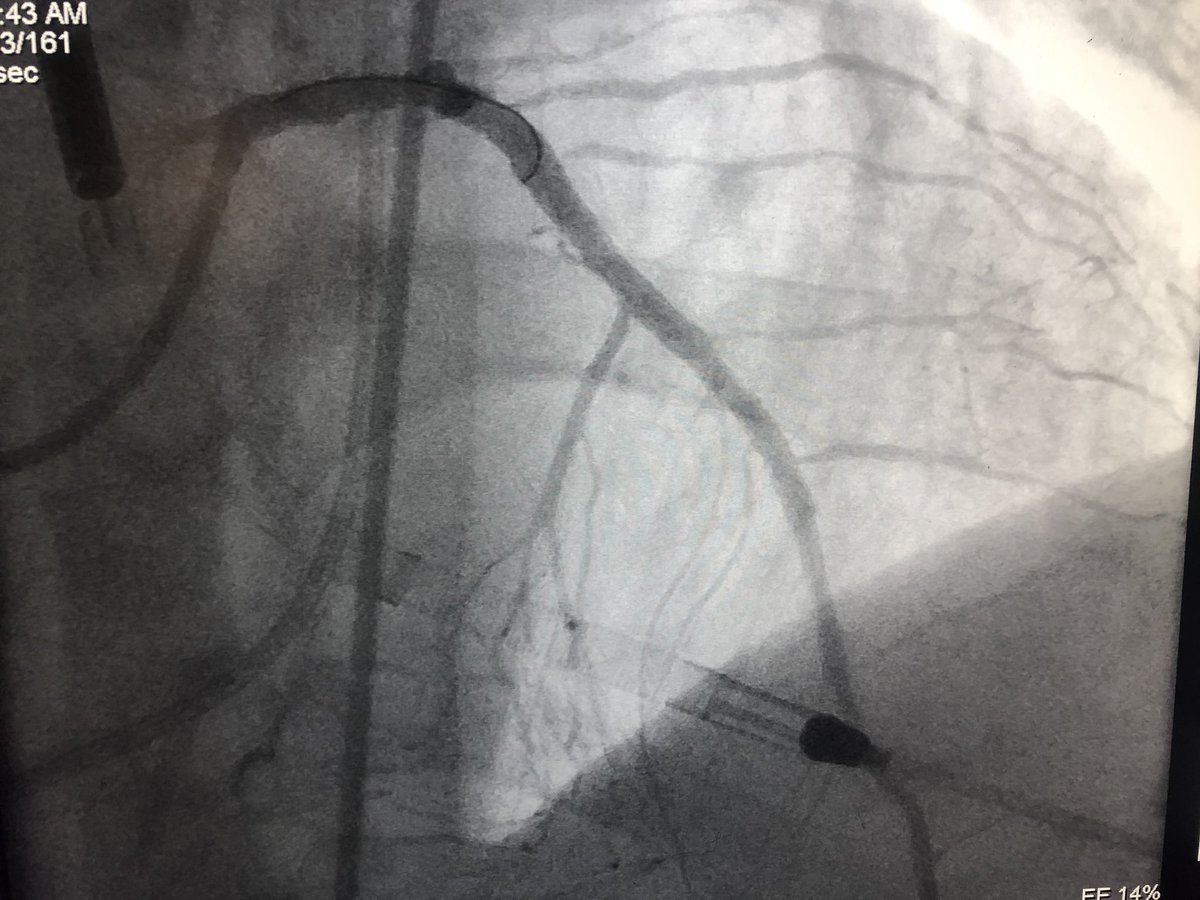

72 y/o WM with AS and LM/MV CAD. Complex bilateral iliac disease. #PercAx for Impella CP. Right ulnar access for DK crush for LM disease with left #radialfirst access for management of left axillary artery. Big thanks to @DrAmirKaki for showing me how.

matheenkhuddus's tweet image. 72 y/o WM with AS and LM/MV CAD. Complex bilateral iliac disease. #PercAx for Impella CP. Right ulnar access for DK crush for LM disease with left #radialfirst access for management of left axillary artery. Big thanks to @DrAmirKaki for showing me how.